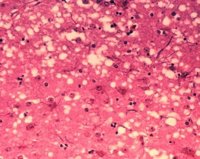

Un estudio llevado a cabo por los investigadores de la Universidad de Castilla-La Mancha (UCLM) Mairena Martín y José Luis Albasanz, junto con otros del Instituto Hospital del Mar de Investigaciones Médicas de la Universidad Pompeu Fabra y el Hospital Charité de Berlín, demuestra, por vez primera, que el colesterol presente en las membranas de las células puede interferir en la función de una importante proteína de las membranas cerebrales a través de un modo de interacción desconocido hasta el momento.

El trabajo, publicado en la revista Nature Communications, revela que el colesterol es capaz de regular la actividad del receptor A2A de adenosina, invadiendo su interior y accediendo así a su centro activo, según ha informado en nota de prensa la UCLM.

Por su parte, según los investigadores, el colesterol es un componente esencial de las membranas neuronales donde residen, entre otras proteínas, los GPCRs, y hasta ahora se creía que el colesterol de membrana podía regular la actividad de estas proteínas mediante dos mecanismos: alterando las propiedades físicas de la membrana o uniéndose a la superficie de la proteína. En ambos casos, se pensaba que el colesterol solo podía ejercer su acción moduladora desde fuera de la proteína.

Sin embargo, ahora este estudio demuestra por primera vez que el colesterol puede ejercer una acción directa sobre los GPCRs y establece las bases de una vía de interacción entre la membrana celular y estas proteínas receptoras y que hasta el momento era completamente desconocida.

El mismo ha permitido demostrar que el colesterol puede abandonar la membrana neuronal y acceder al interior del receptor de adenosina, en concreto a su centro activo, modulando así su funcionalidad.

Así, un nivel elevado de colesterol en la membrana podría favorecer el bloqueo de los receptores de adenosina, lo que podría explicar algunos síntomas observados en la enfermedad de Alzhéimer.